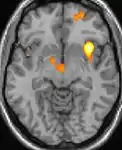

![]() | ![]() | ![]() |

| Voxel-based morphometry (VBM) shows brain area structural differences. | ||

Positron emission tomography (PET) scans indicate the brain areas which are activated during attack only, compared to pain free periods. These pictures show brain areas that are active during pain in yellow/orange color (called "pain matrix"). The area in the center (in all three views) is specifically activated during CH only. The bottom row voxel-based morphometry (VBM) shows structural brain differences between individuals with and without CH; only a portion of the hypothalamus is different.[36]